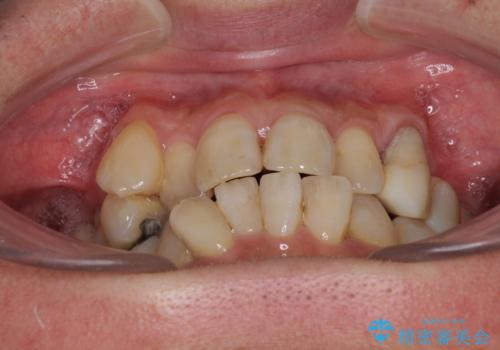

- 歯並びやグラグラする奥歯など、気になる所を全部治したいとのことで来院された患者様です。

奥歯は咬み合わせや歯周病により歯槽骨が失われていたり、むし歯や破折している歯などがあったりと、歯周病治療やインプラント補綴、矯正治療など、総合的に治療が必要と診断されました。

まずは歯周病治療やインプラント埋入を行い、環境が整った後にワイヤーを併用したインビザライン矯正を行い、オールセラミッククラウンにて補綴治療を行うこととしました。